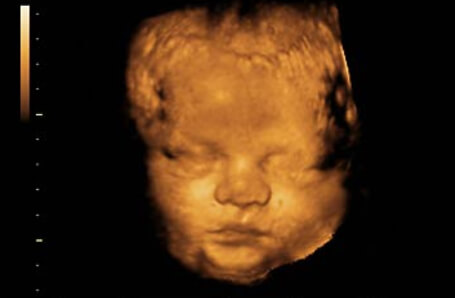

39 Haftalık Bebeğin Ultrason Görüntüsü

Gebelikte 38. hafta yazımızda da belirttiğimiz gibi, hamileliğin son haftalarında bebeğinizin ultrason görüntüleri de internette karşılaştıklarınızdan oldukça farklı olmaya başlayacaktır; çünkü artık bebeğinizin fiziksel özellikleri oturdu ve bambaşka bir birey olarak doğumu bekliyor.

• 39. haftadaki ultrason görüntünüzde bebeğinizin baş aşağı durduğunu ve doğum pozisyonu alarak kasıklara indiğini görmeniz gerekmektedir.

• Eğer bebeğiniz henüz baş aşağı dönmemiş ise, doktorunuzun size randevu vermiş olması ve doğum pozisyonu için aksiyon almaya hazır olmanız gerekmektedir.

• 39 haftalık bebeğinizin, yenidoğan bir bebek gibi uyumakta, hıçkırmakta, göbek kordonu ile oynamakta ya da parmaklarını emmekte iken ultrasona yakalanması olağandır.